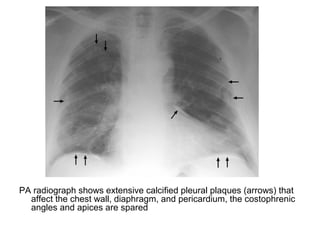

PA radiograph shows extensive calcified pleural plaques (arrows) that

affect the chest wall, diaphragm, and pericardium, the costophrenic

angles and apices are spared